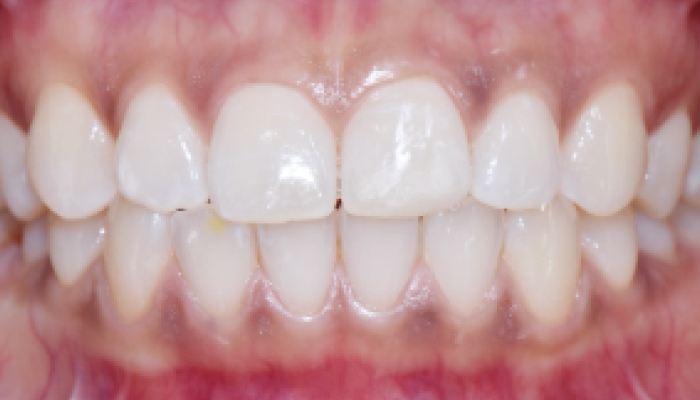

다양한 합병증을 동반하는 이갈이